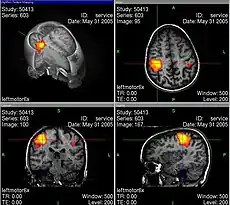

Si se necesita ver qué áreas del cerebro intervienen cuando se mueve, por ejemplo, la mano derecha, se introduce a un voluntario, con la instrucción de mantenerse completamente inmóvil dentro del aparato, y mover únicamente los dedos cuando se le indique. Durante tres minutos el voluntario hará movimientos de los dedos en forma intermitente. El aumento de actividad en las áreas cerebrales relacionadas con esta tarea causará una vasodilatación y un aumento del flujo sanguíneo en estas mismas áreas. Este aumento del flujo/volumen es detectado por el resonador y normalmente representado en una imagen. En esta imagen se muestra en escala de grises la estructura del cerebro obtenida mediante resonancia magnética (no funcional) y en color la zona activada.